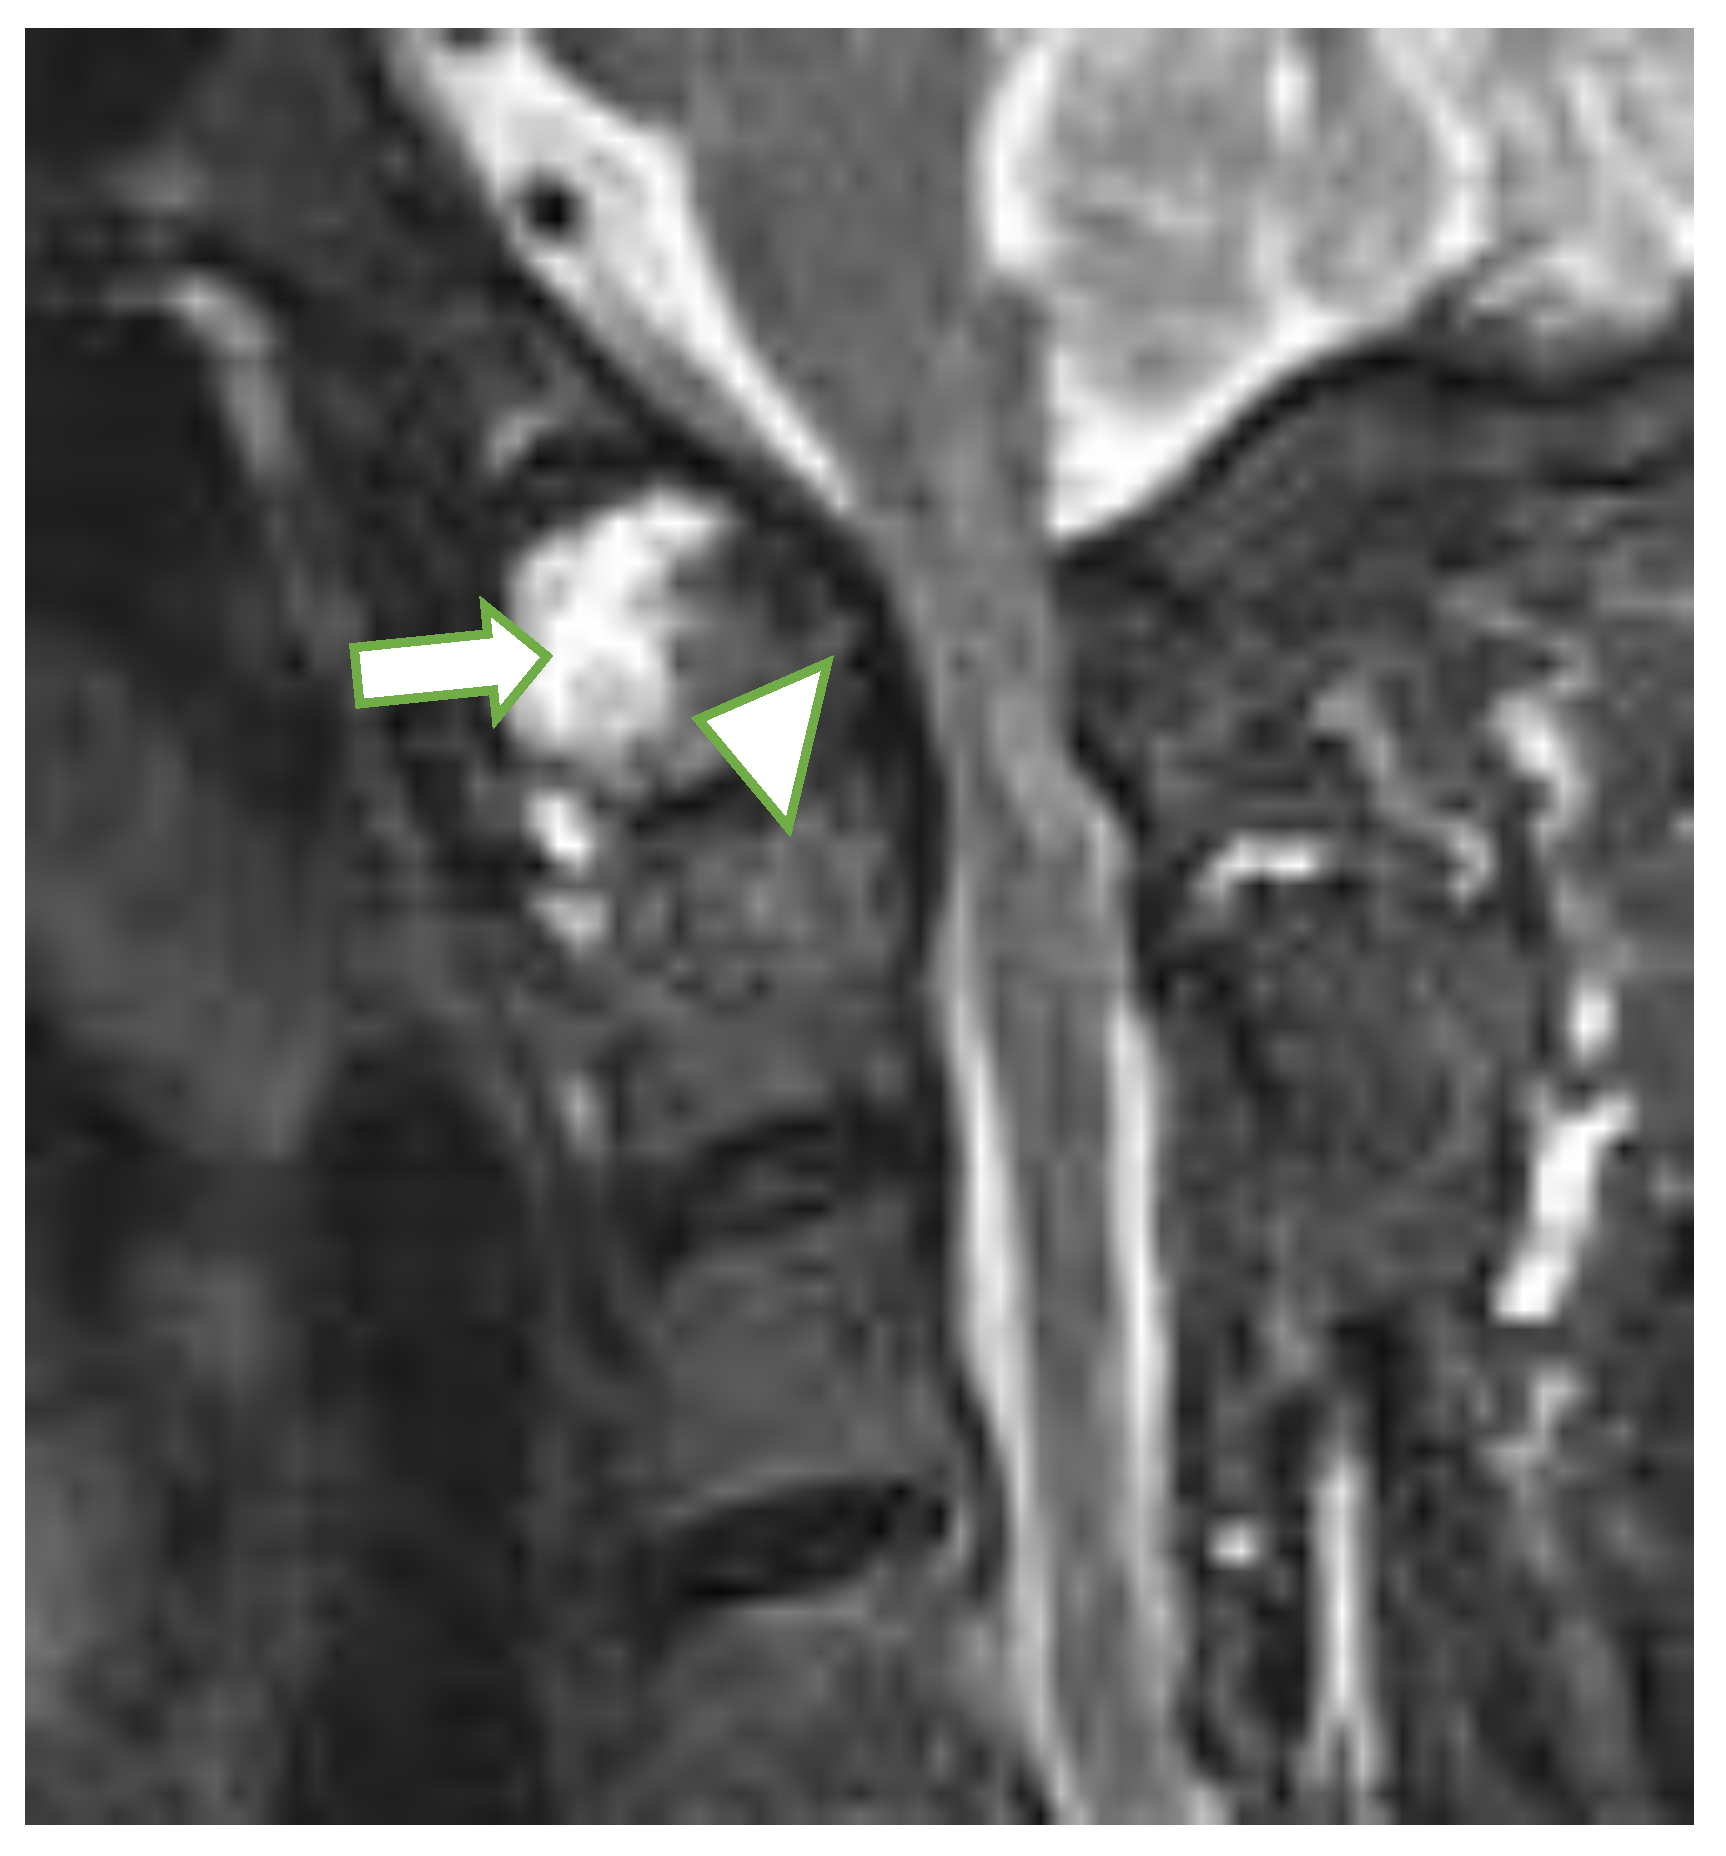

At the C1/C2 level, the most frequently diagnosed abnormalities (apart from anterior AAS) were (Table 1) vertical AAS (25 [10%] seen on MRI, 27 [11%] on radiography), posterior AAS (11 [5%]) and lateral AAS (7 [3%]); the latter two were observed only with MRI. Dens erosions were seen in 36 patients (15%; Figure 2) on MRI, while radiography showed dens erosions in 11 subjects. With MRI only, pannus was diagnosed in 50 patients (21%; Figure 3), periodontal effusion in 26 (11%), BME in 11 (5%), and contrast enhancement of bone (osteitis) and/or synovium in 12 (5%) patients. MRI showed brain steam compression in eight patients (3%).

Figure 2.

Sagittal MRI, T2-w TIRM image in a 65-year-old female with rheumatoid arthritis shows dens erosions (arrowhead) and periodontal effusion and pannus (long arrow). MRI: magnetic resonance imaging, TIRM: turbo inversion recovery magnitude.